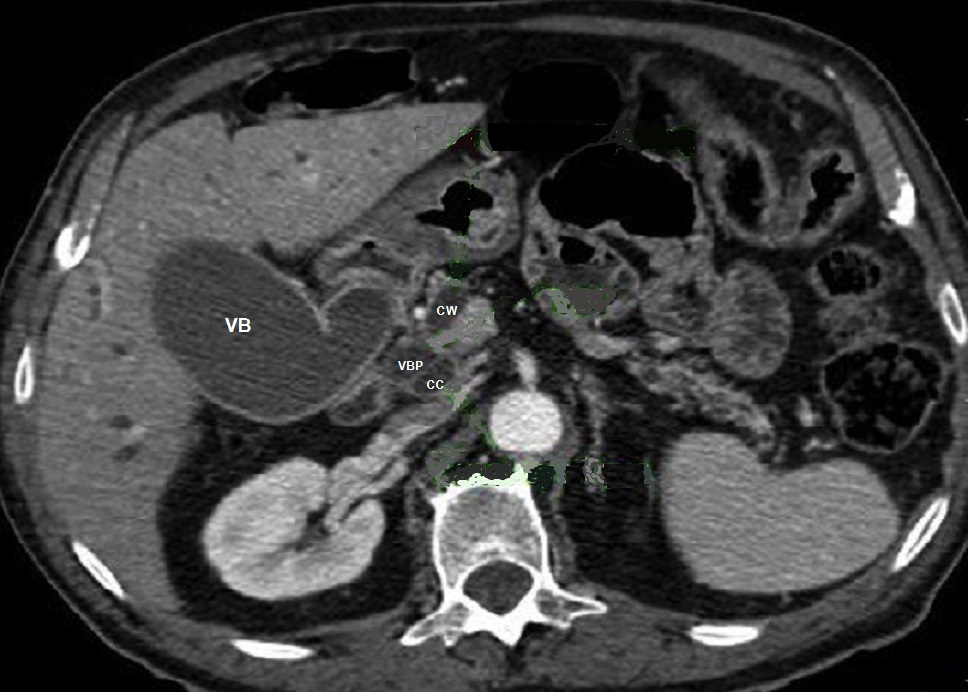

Image

radiologique de dilatation du VBP et des voies

biliaire intrahapatique d'une tumeur de la tete

dupancreas . Coupe TDM axiale . |

Image de distention legere

de la vesicule biliaire ( VB ) et de voie biliaire

principale ( VBP ) . |